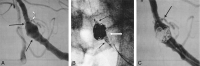

Results: All five cases (100%) were technically successful without complications. In each case, the stent was accurately placed in the desired location, immediately followed by coil embolization to the desired degree of occlusion with a satisfactory result. The poststent and coil-occlusion angiogram demonstrated excellent blood flow across the stent, with satisfactory positioning of the coils within the aneurysm in all cases (100%). No patient suffered any clinical or neurologic complications, and all were discharged 1-3 days postprocedure, in stable condition with no new neurologic deficits.

Conclusion: In early clinical studies, the Cordis Enterprise stent performed well. The stent was able to be well visualized, deployed easily, could be repositioned if needed, and was accurately placed without technical difficulties. The closed cell design allowed all coils to be placed within the aneurysm and remain outside the flow of the parent artery. No periprocedural complications were encountered.